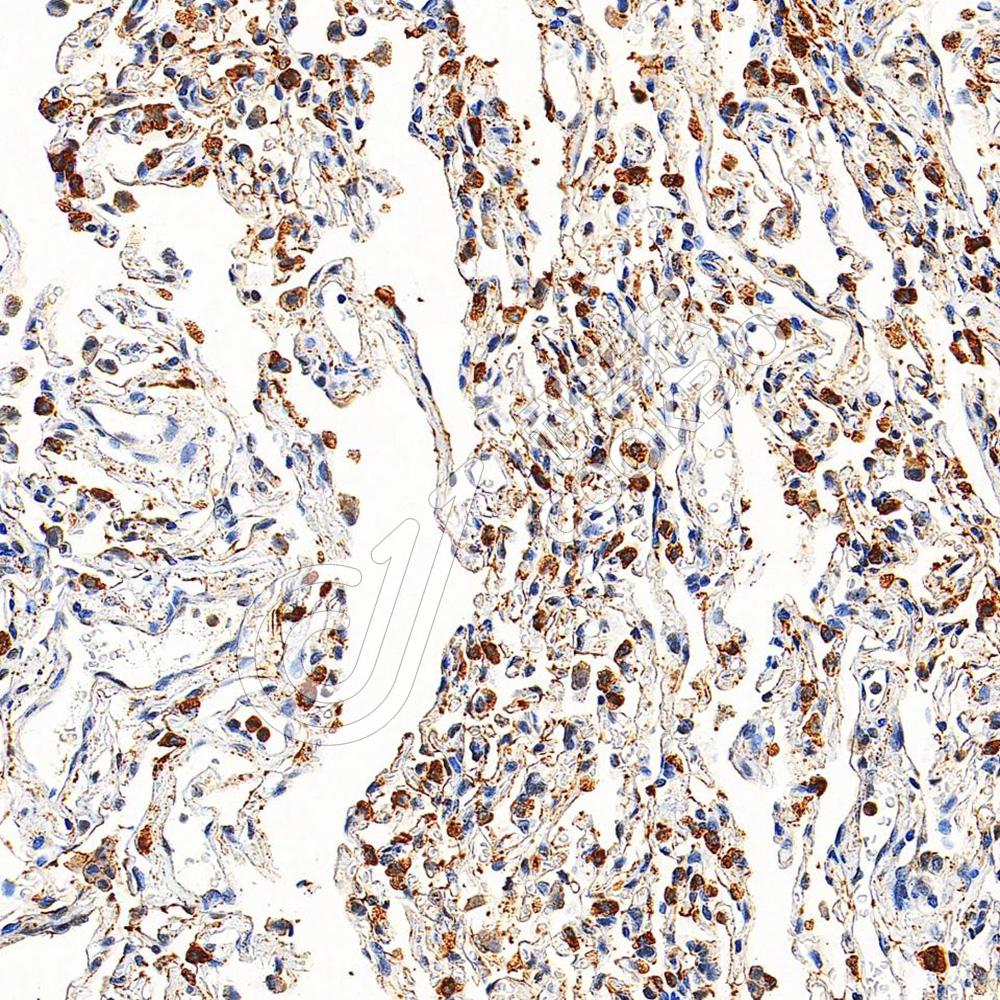

IHC检测SFTPA1蛋白(货号 K1342495).

样品: 人肺, 4%多聚甲醛 (货号KSG1101) 固定12-24小时.

抗原修复: 柠檬酸抗原修复液(干粉, pH 6.0) (KSG1201), 98℃, 20分钟.

—抗: 1: 1500稀释, 4℃ 孵育过夜.

二抗: S-vision免疫组化多聚二抗(山羊抗兔),即用型 (货号KB3906), 室温孵育20分钟.